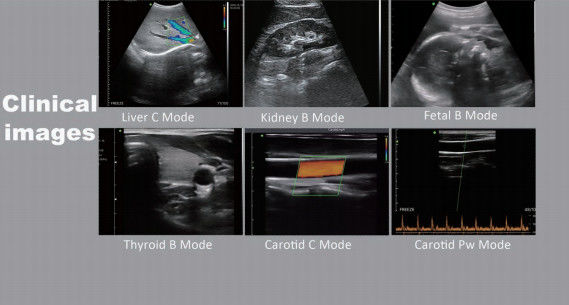

Handheld USB Convex Wireless Ultrasound Probe Medical Doppler 3.5-5 Mhz For Adroid Images |